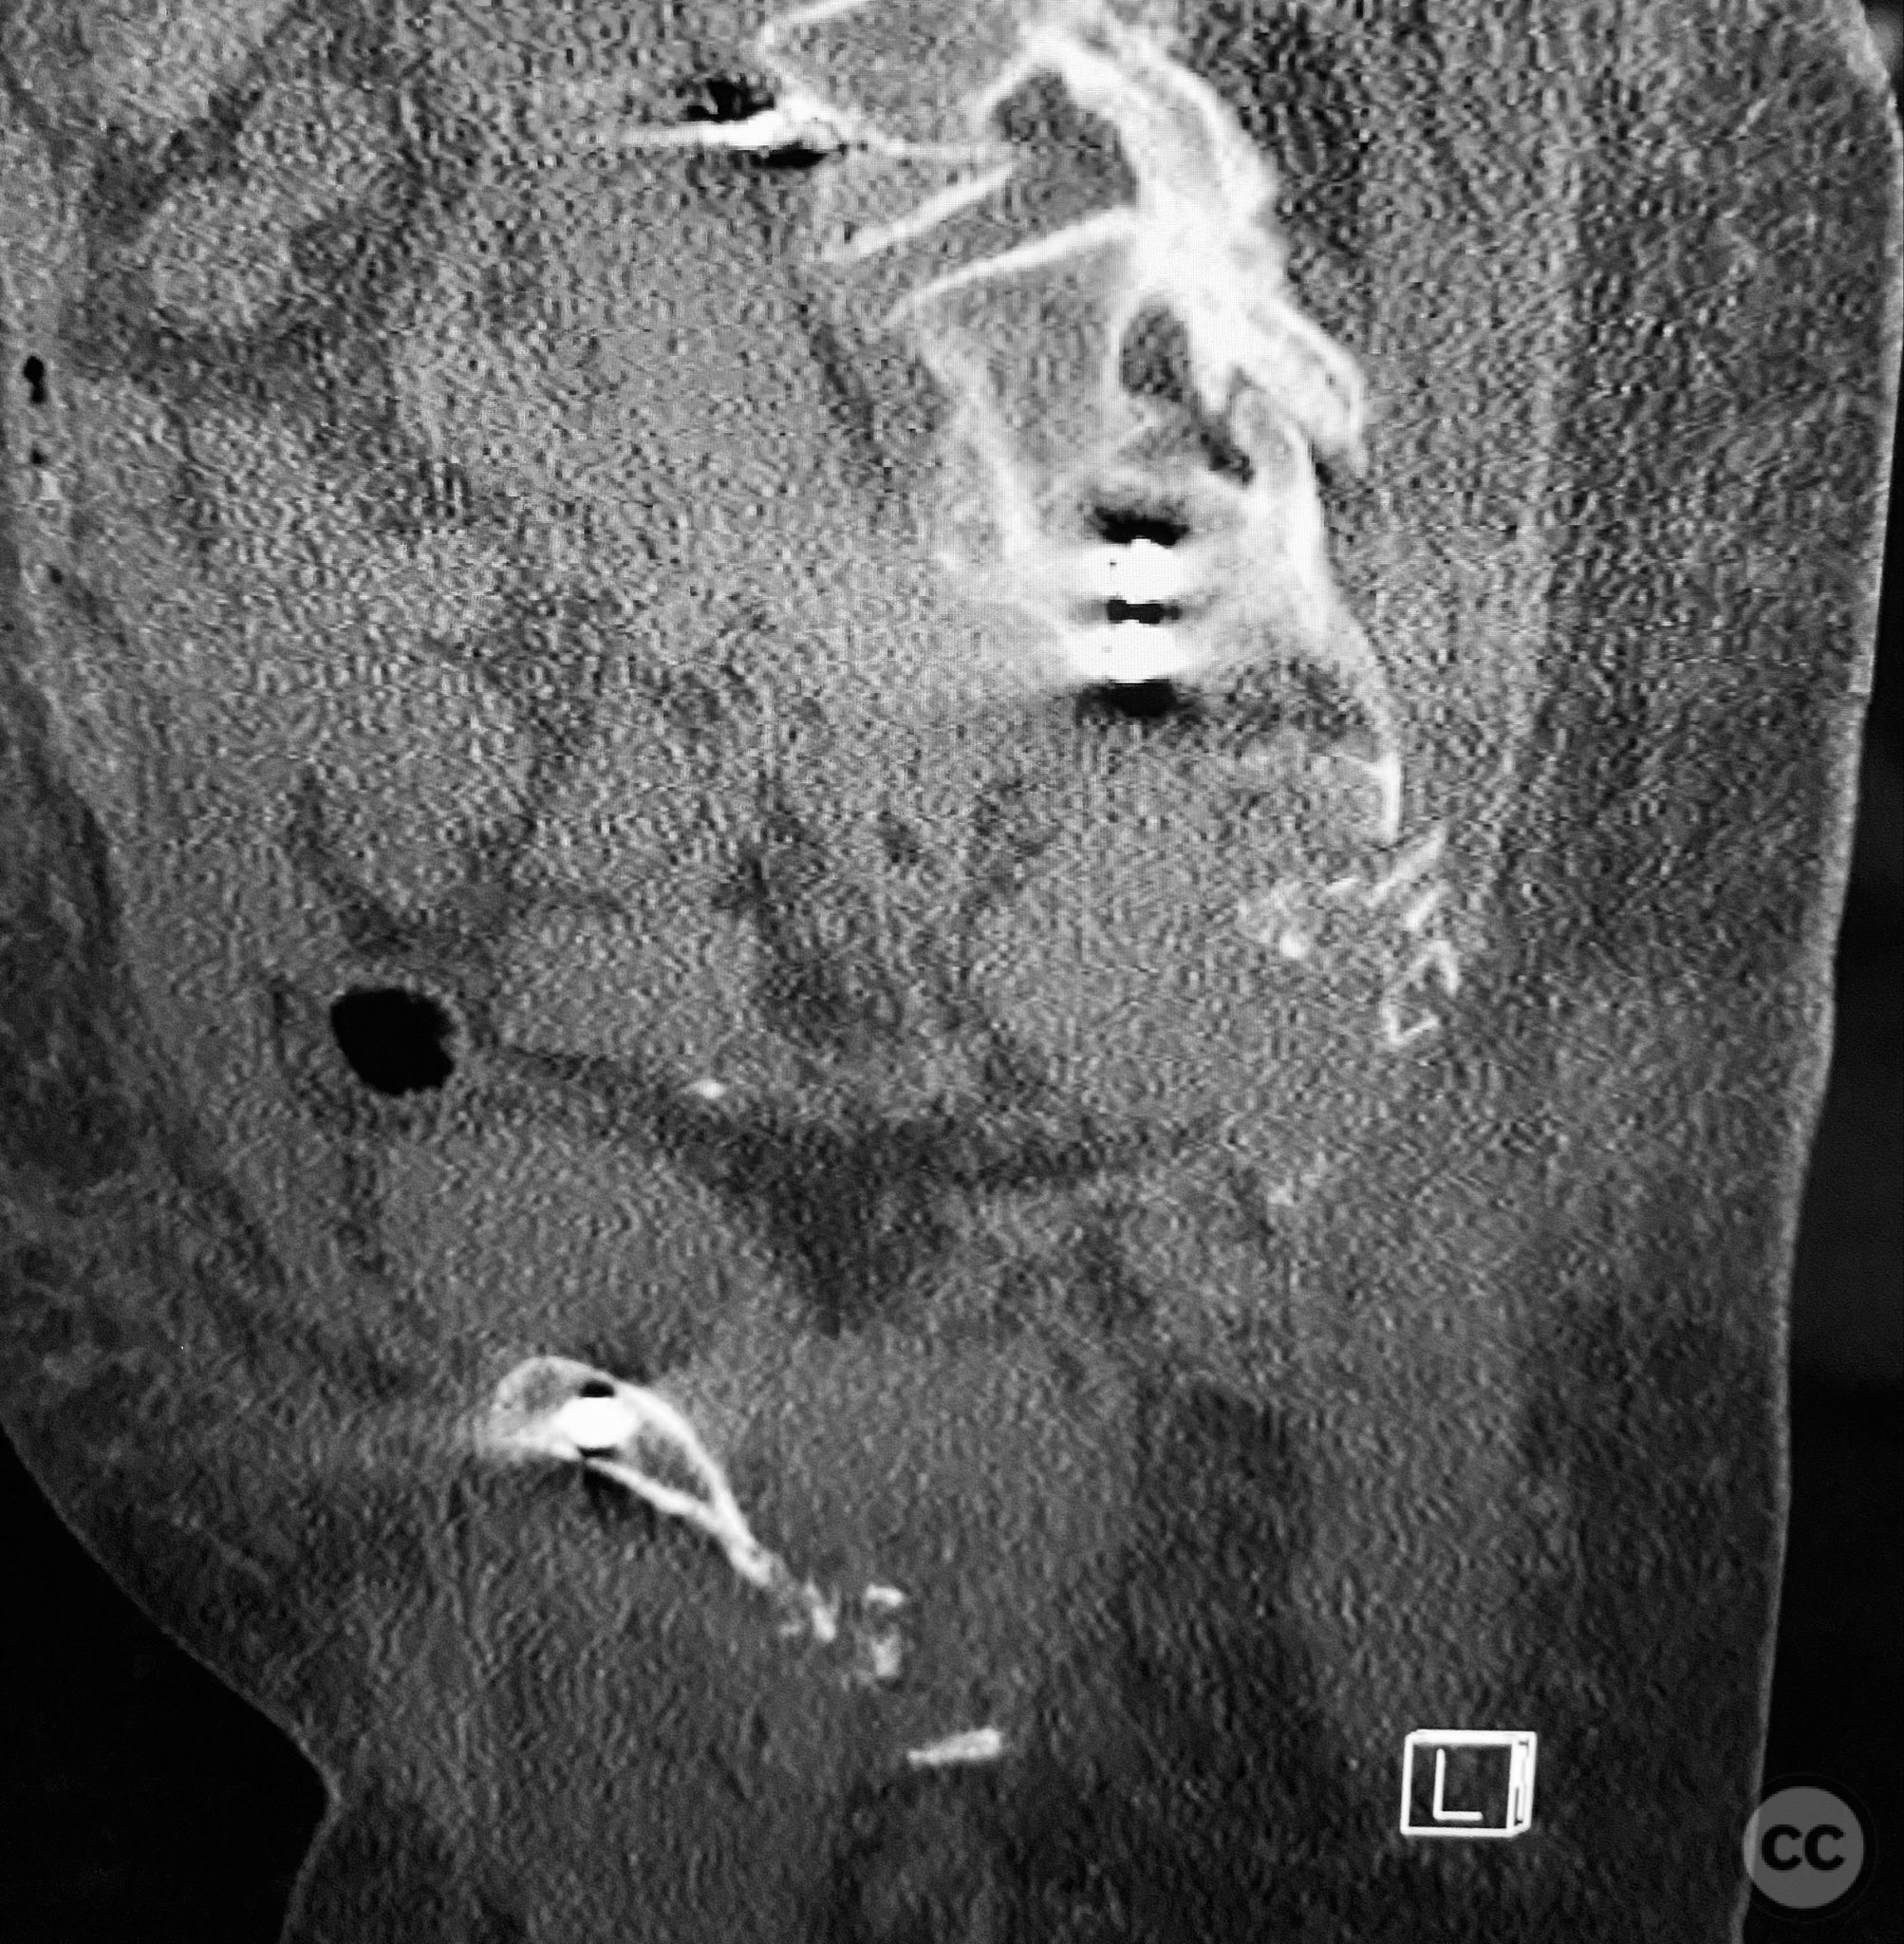

Clinical and radiological findings:  An elderly patient sustained multiple traumatic injuries, including complex unstable pelvic ring disruption (AO/OTA 61-C, likely C1 or C2 based on instability and comminution), comminuted proximal femoral fracture (AO/OTA 31-A3 or 31-B, depending on trochanteric or neck involvement), and significant abdominal trauma necessitating intra-abdominal packing. Initial clinical evaluation revealed hemodynamic instability and poor bone quality consistent with advanced age. Distal femoral traction was applied for provisional reduction. Radiological assessment was limited by osteopenia, fracture comminution, and the presence of abdominal packing materials.

Planning remarks:  The preoperative plan included early closed reduction maneuvers under fluoroscopic guidance, percutaneous stabilization of the pelvic ring with cannulated screws, and intramedullary nailing of the proximal femur. The anatomical approach for pelvic fixation was percutaneous iliosacral screw placement; for the femur, a standard antegrade intramedullary nailing technique was planned.

Anatomical surgical approach:  Percutaneous iliosacral screw fixation was performed through small lateral gluteal incisions, with blunt dissection to the outer table of the os ilium. Under fluoroscopic guidance, guidewires were advanced across the sacroiliac joint into the S1 body, followed by cannulated screw insertion. For the proximal femur, a longitudinal incision was made proximal to the greater trochanter, splitting the fascia lata and gluteus medius fibers to access the piriformis fossa. A guidewire was inserted into the medullary canal, followed by sequential reaming and insertion of an intramedullary nail.

Intraoperative imaging was challenging due to osteopenic bone, fracture comminution, and interference from abdominal packing. Accurate identification of safe osseous corridors for iliosacral screw placement required multiple fluoroscopic projections and careful attention to pelvic landmarks. Bone quality necessitated cautious screw advancement to avoid iatrogenic cortical breach. After pelvic fixation, intramedullary nailing of the proximal femur proceeded without complication. Abdominal packing was removed and laparotomy wound closed after skeletal stabilization. Early mechanical stabilization of both pelvic and femoral injuries was prioritized to optimize survivability in this multiply injured elderly patient.